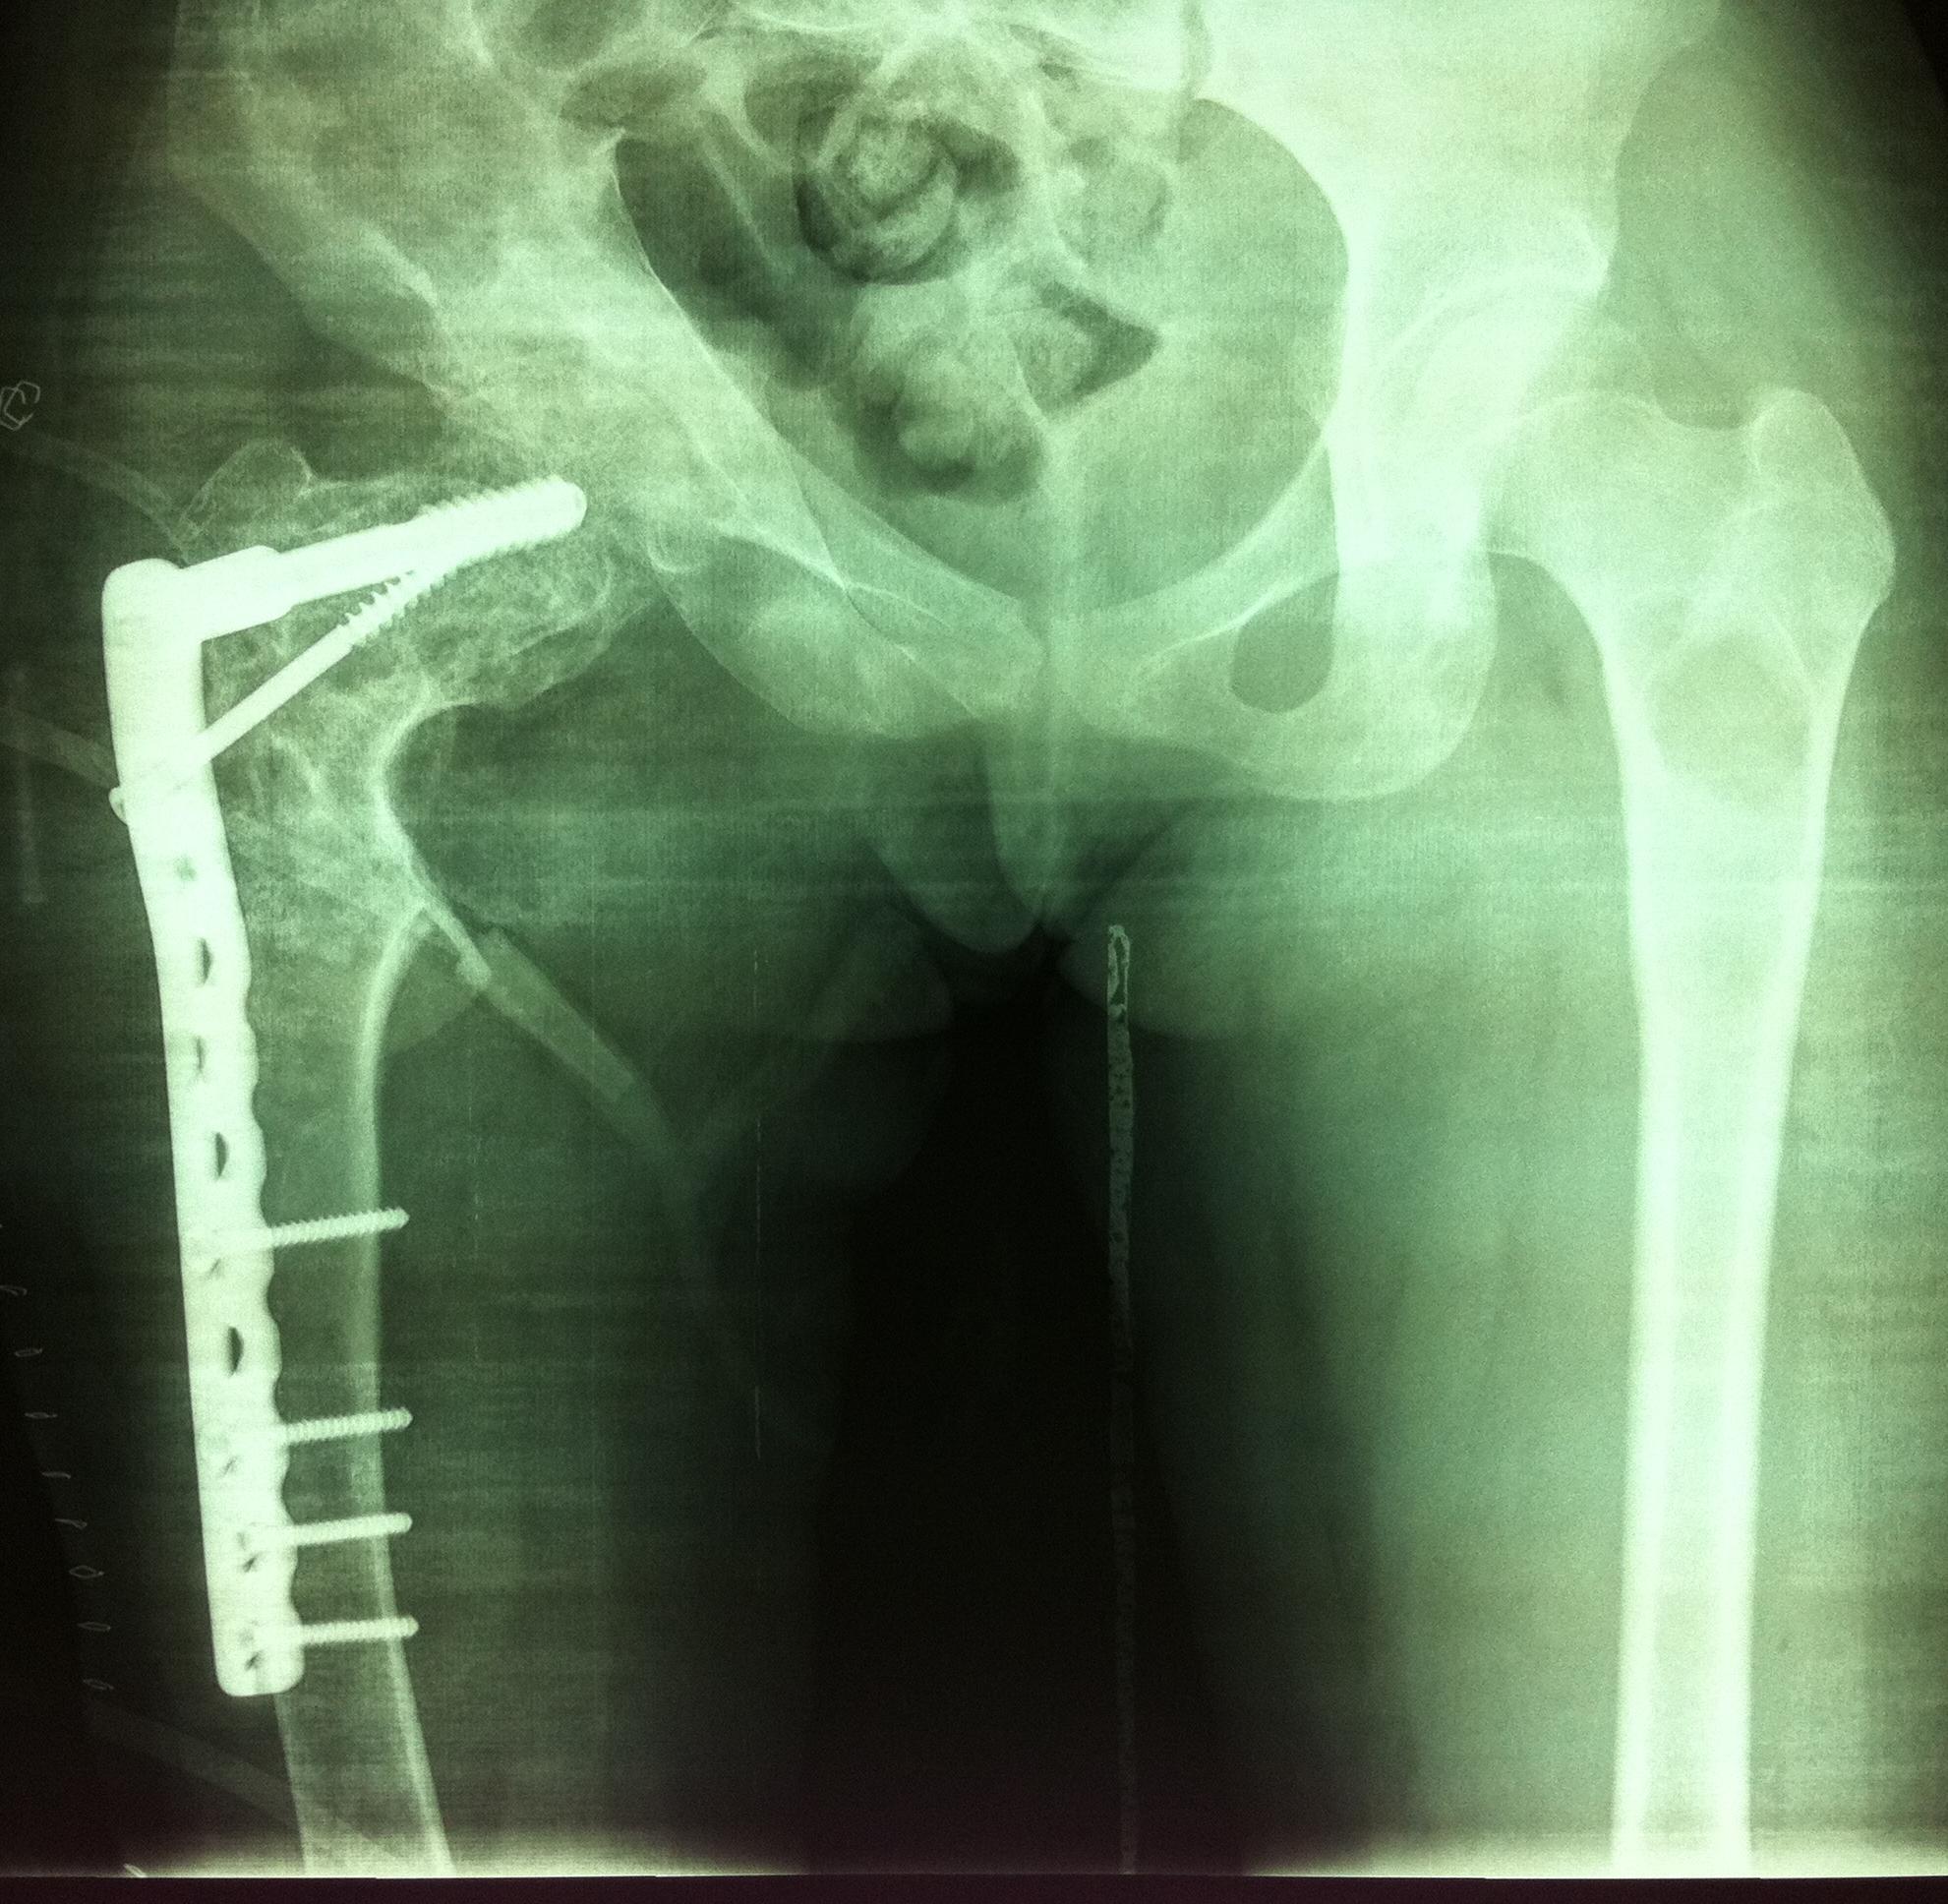

图4 女性,17岁,术前肢体短缩4cm图5 术后2年复查肢体等长,截骨处愈合